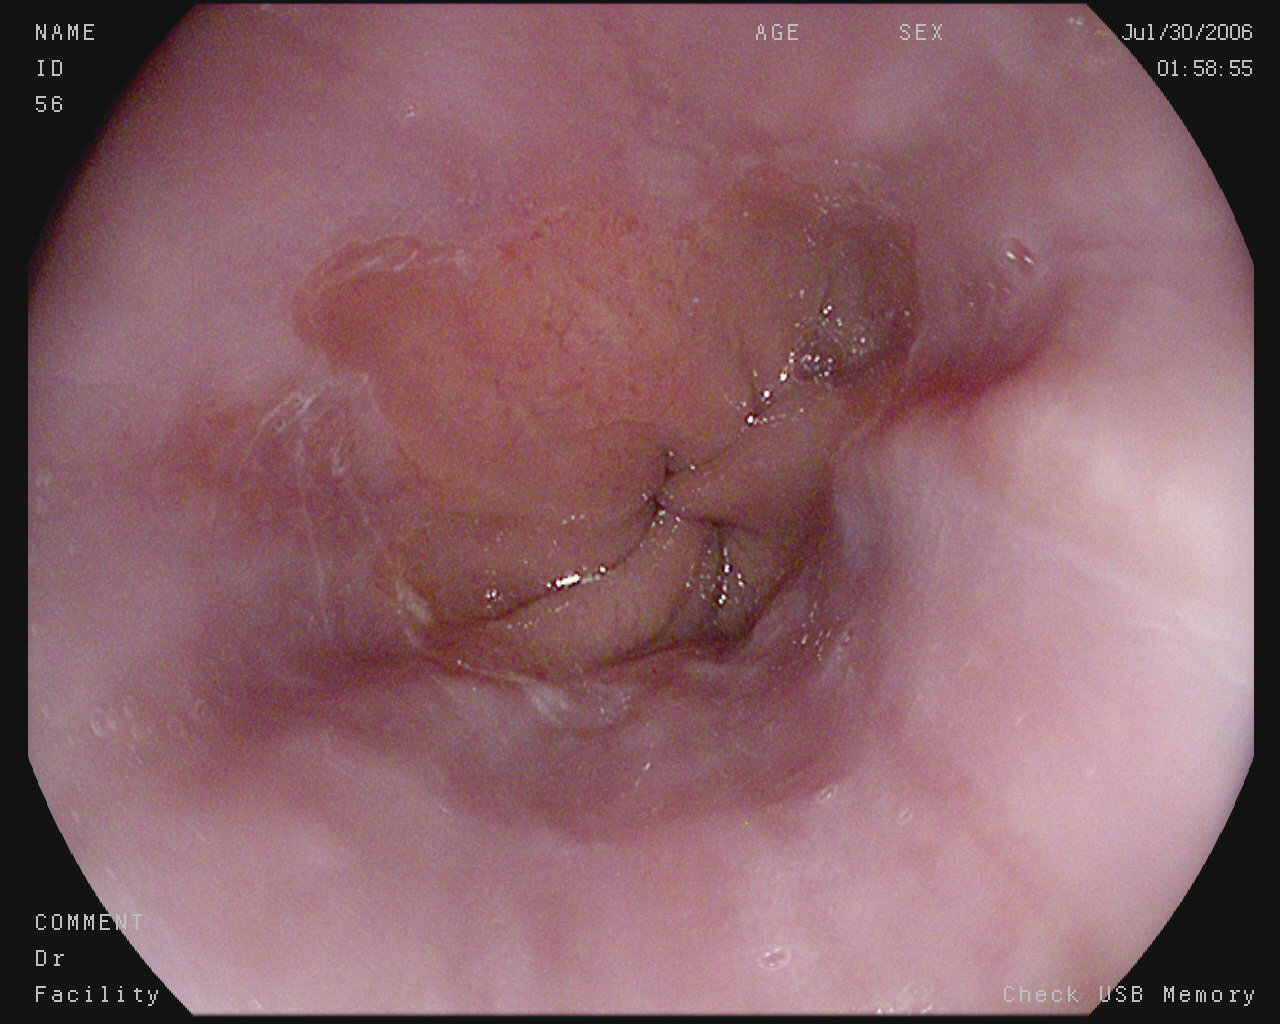

The Kvasir Dataset

Polyps

Ulcerative colitis

Normal cecum

Esophagitis

Normal z-line

Normal pylorus